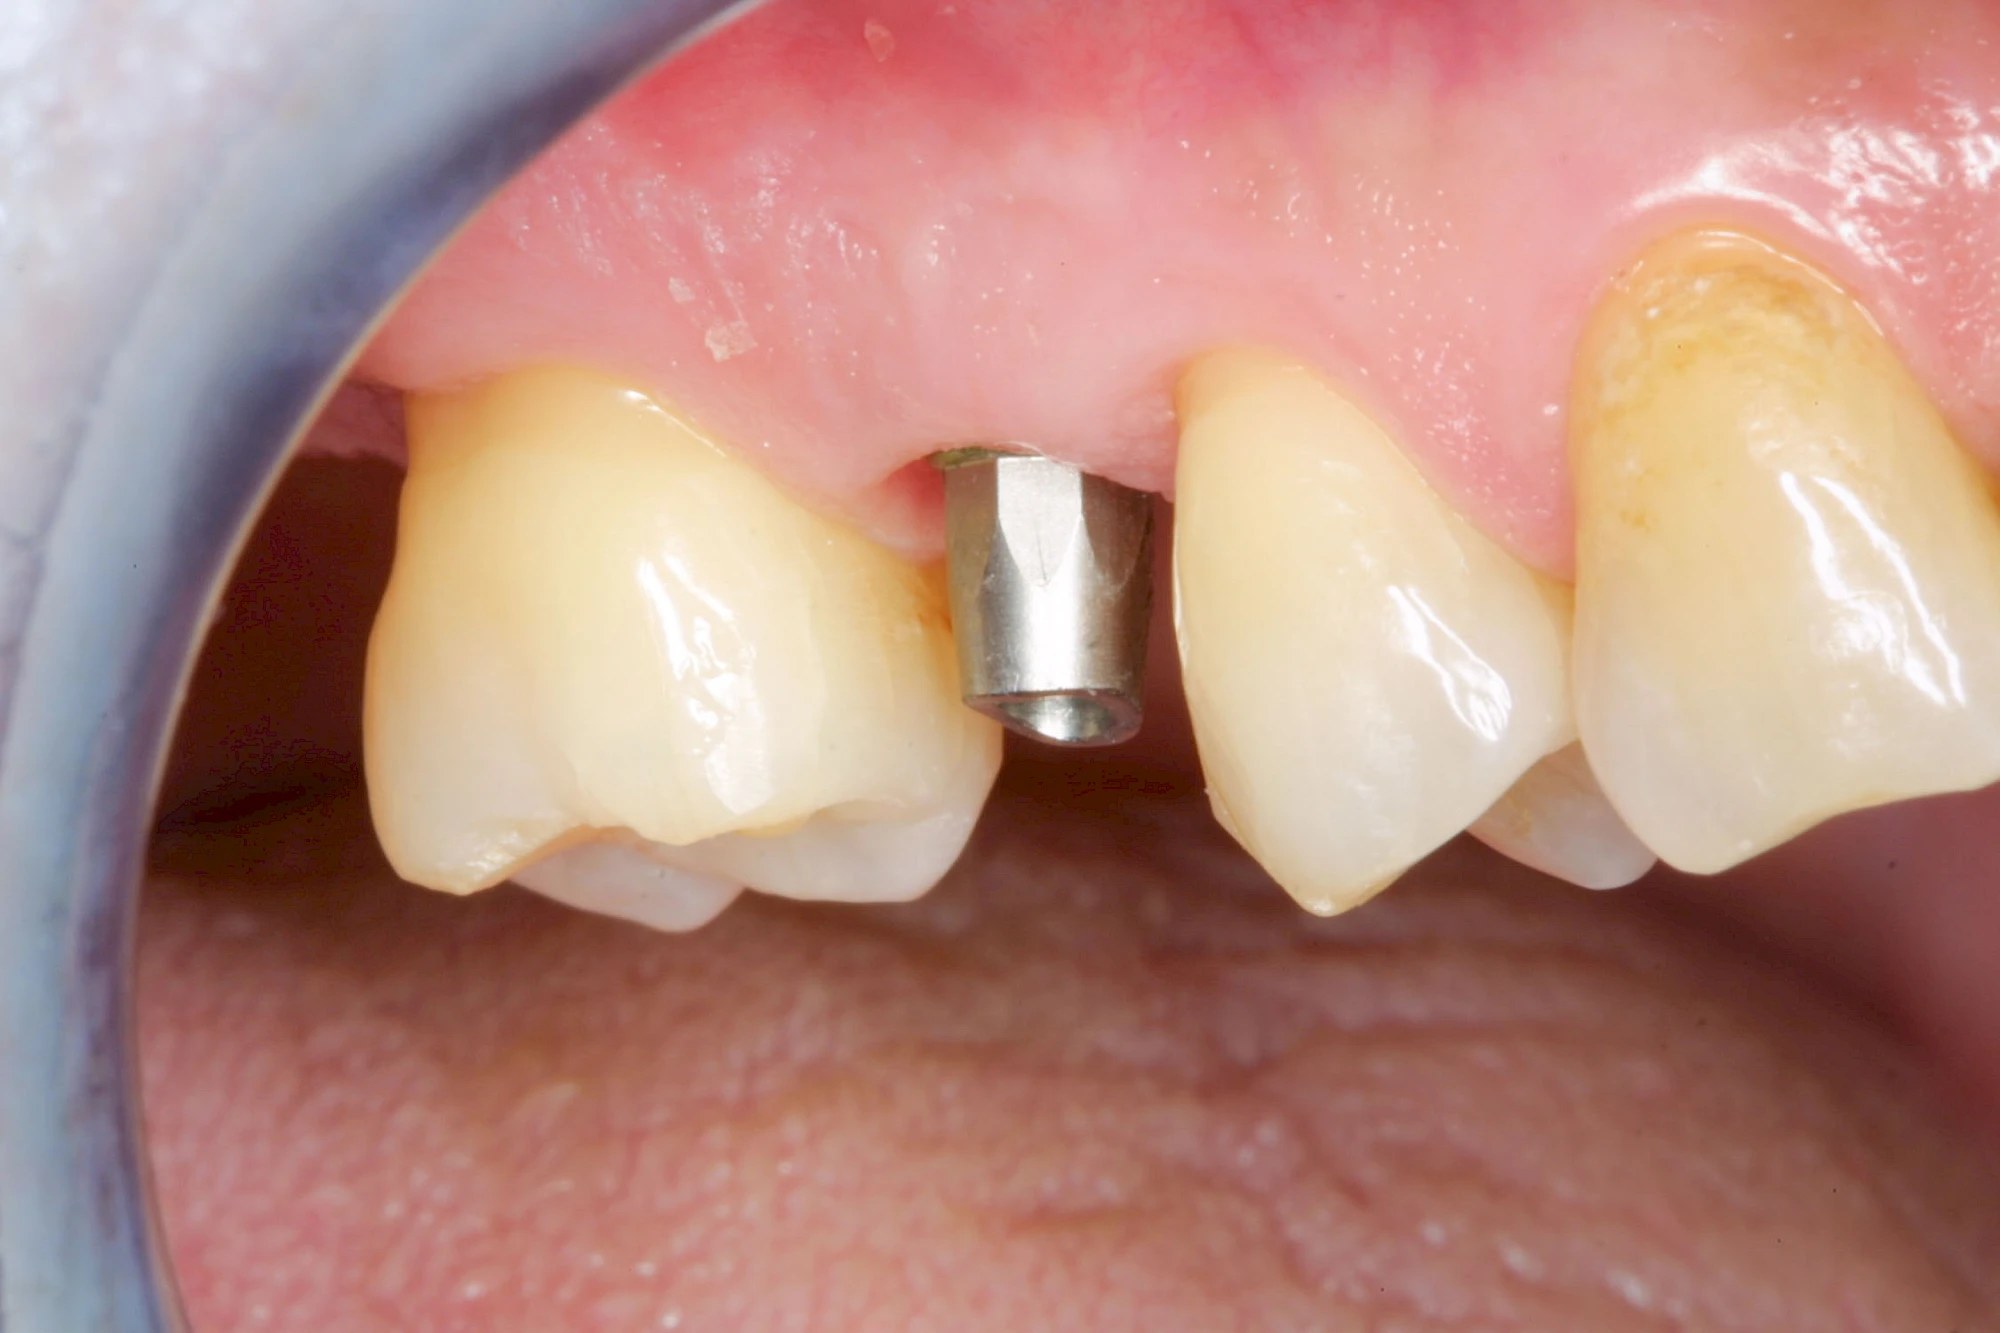

Implantate sind künstliche Zahnwurzeln. Nach einer gewissen Einheilzeit im Knochen (meist 3-6 Monate) erfolgt über einen separaten Aufbau (Abutment) die Befestigung einer Krone bzw. Brücke oder Zahnprothese.

In seltenen Fällen sind Implantate samt Aufbau aus einem Stück gefertigt. Auch gibt es Situationen, die ein Früh- oder sogar eine Sofortbelastung erlauben – dann kann die Einheilzeit der Implantate in den Knochen verkürzt oder sogar gänzlich darauf verzichtet werden.

Implantate: Kronen & Brücken

Fehlen einzelne Zähne und die Nachbarzähne sind unbeschadet oder gut zahnärztlich versorgt, werden immer häufiger Implantate gewählt, um die Lücken zu schließen. Auch bei größeren oder verteilten Lücken, wenn keine herausnehmbare Prothese gewünscht ist, werden Implantate für Kronen- bzw. Brückenversorgungen gesetzt. In Einzelfällen entscheiden sich sogar zahnlose Patienten für eine festsitzende Versorgung auf Implantaten.

Varianten zur Verankerung von festsitzendem Zahnersatz auf Implantaten